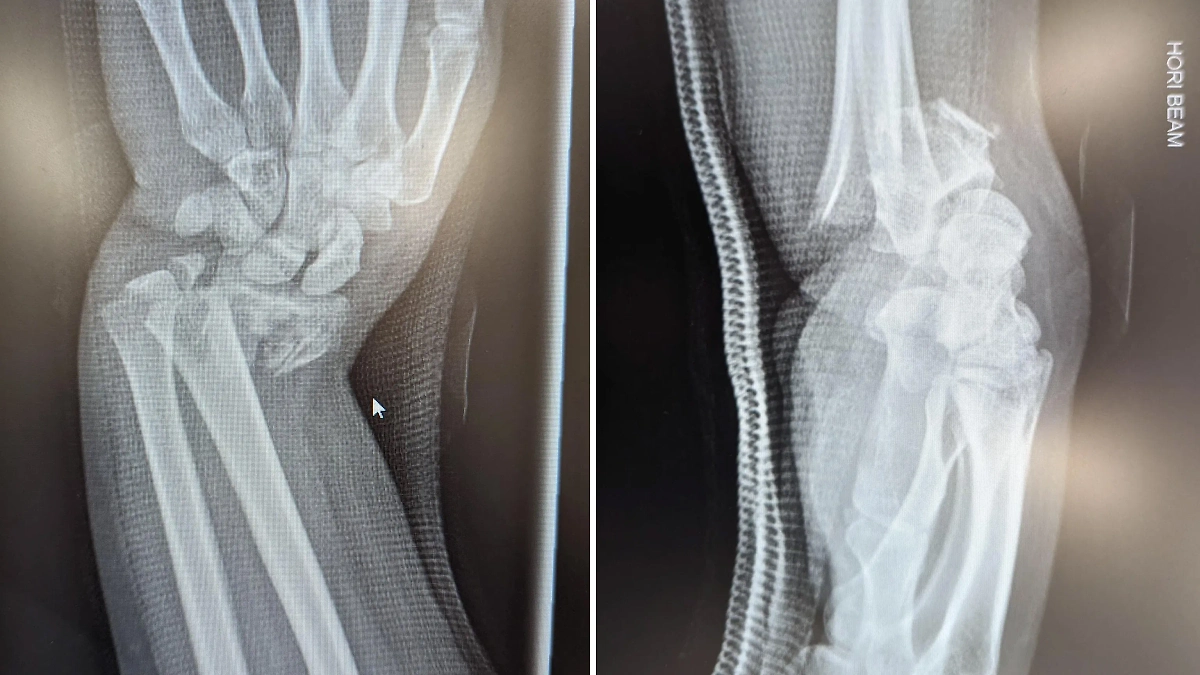

"Всего лишь пять дней с начала года, а уже сломал руку и ногу", — alivesarcasm.

Фото © Reddit / alivesarcasm